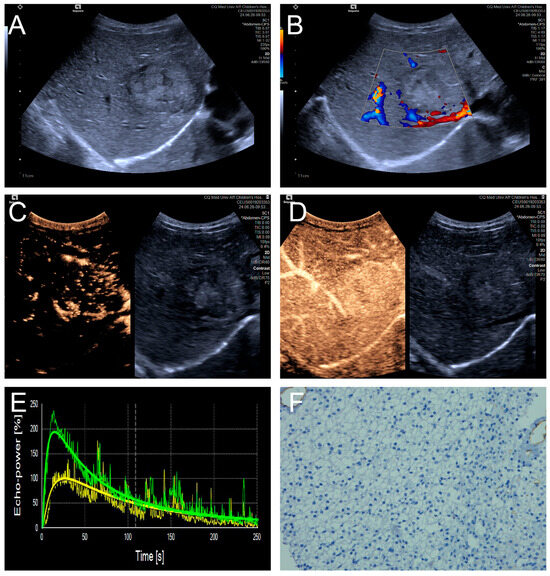

3.3. Qualitative CEUS Performance of HB Lesions: High and Low MVD Groups

Penetrating vessels were significantly more frequent in the high MVD group (p < 0.05). In contrast, no significant differences were observed between the two groups regarding enhancement uniformity or enhancement order (p > 0.05). Representative CEUS features are illustrated in Figure 3 and Figure 4, and the comparative results are summarized in Table 4.

Figure 4.

(A–F) A male patient aged 10 years and 6 months with HB and high MVD. (A) The imaging revealed a lesion with unclear margins and hyperechoic echogenicity in the liver’s left lobe; (B) During the enhancement phase, CDFI revealed abundant vascular signals within the tumor tissue, classified as grade III by Adler; (C,D) The CEUS exhibited non-uniform enhancement progressing from periphery to center, with non-enhancing regions (triangles) within the lesion and peripheral penetrating vessels (arrows); (E) TIC curves showed contrast enhancement of the lesion (green) and perfusion of the adjacent liver parenchyma (yellow). Jagged lines indicated raw signal data, and smooth lines indicated the fitted curves; (F) The biopsy specimen’s cytological immunohistochemical staining revealed dense microvessels (CD34 staining × 200), and the MVD measured 42 lines/HPF.